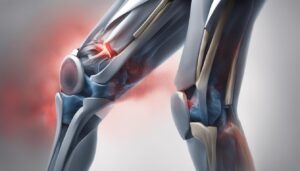

Does Omega 3 Help Arthritis? Learn How Omega 3 Fatty Acids Can Improve Joint Health & Curb Inflammation

Are you suffering from arthritis and searching for natural ways to alleviate your symptoms? Look no further than omega-3 fatty acids. These essential nutrients have